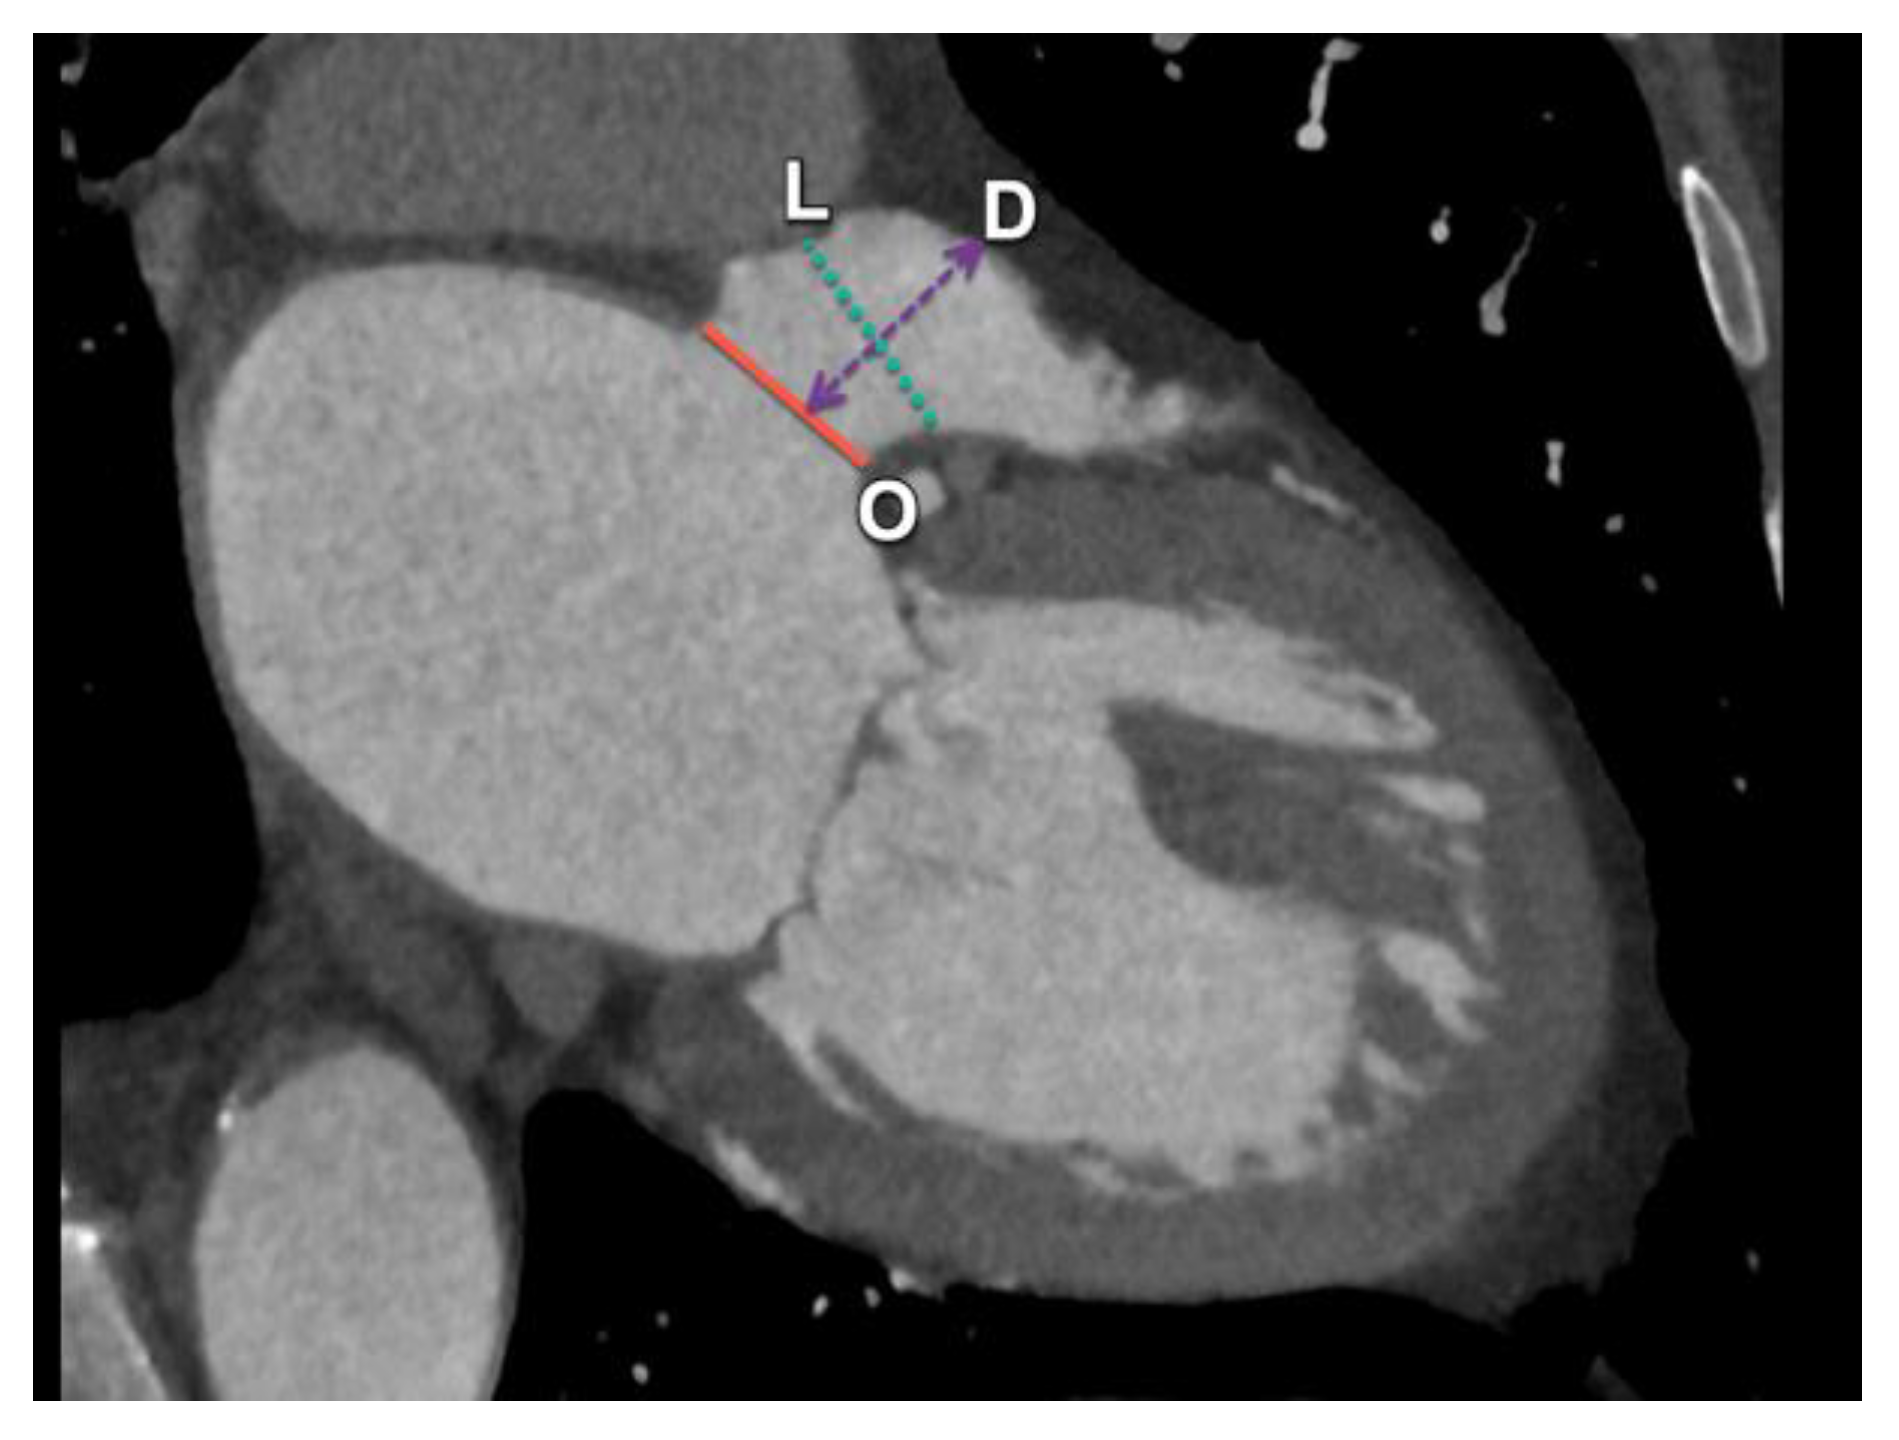

| Coaptation depth | Distance from the annular plane to the point of leaflet coaptation | Should be ≤11 mm for optimal results |

| Coaptation length | Extent of the leaflet overlap | Ideally ≥2 mm for successful clipping |

| Interatrial septum | Thickness and location of the fossa ovalis | Guides the trans-septal puncture site |